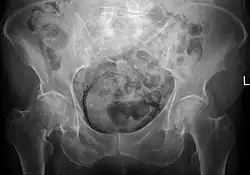

| Regulation of urine production by ADH and aldosterone | |